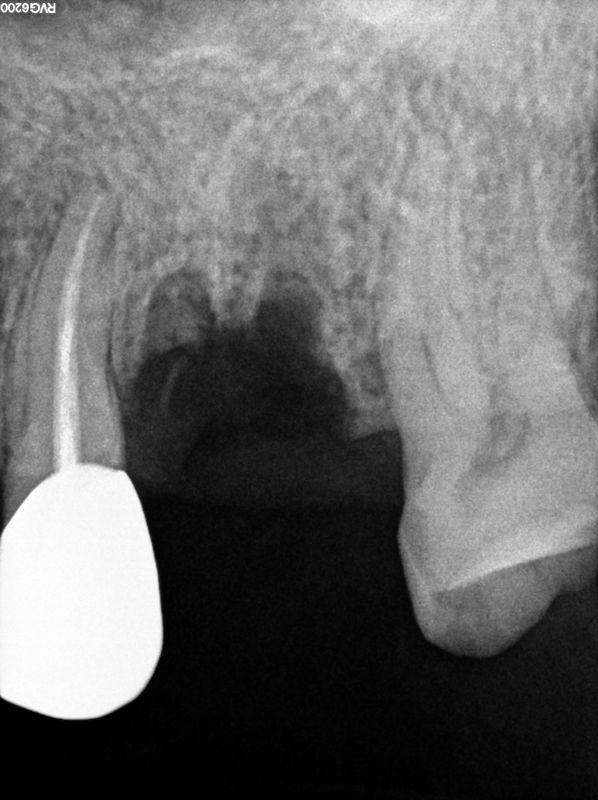

fredlibc | all galleries >> Galleries >> RYang - immediate 26 and apico 25 > R1.jpg

R1.jpg